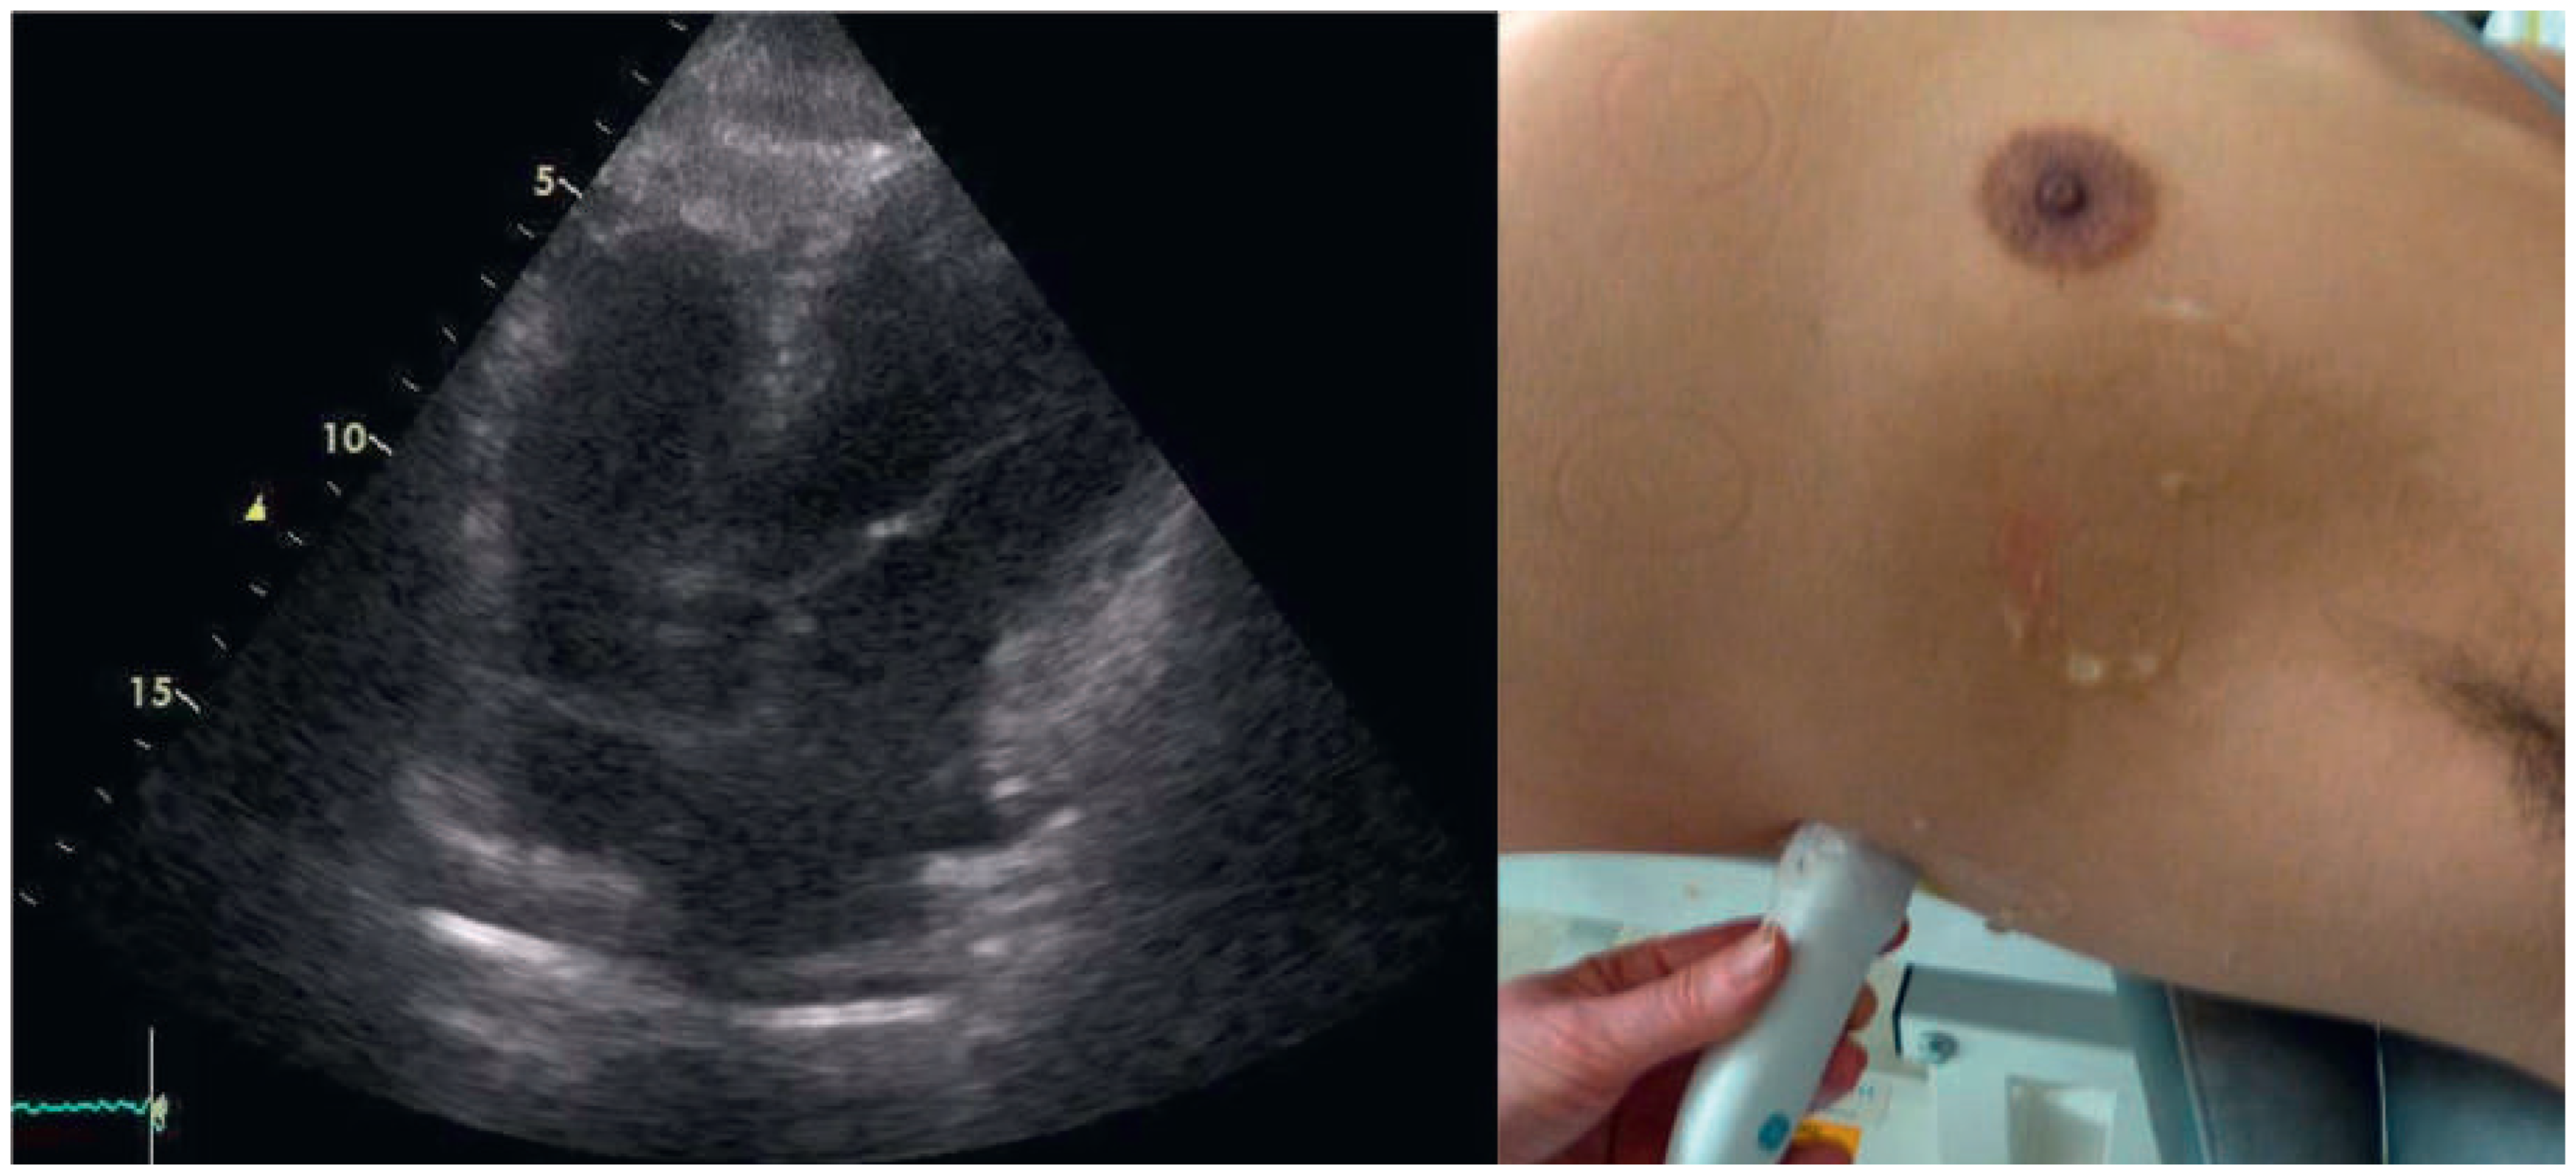

A 57-year-old male presented to the medical outpatient department with typical angina pectoris Canadian Cardiovascular Society (CCS) class II and dyspnoea on exertion during the previous weeks. Additionally he had retrosternal pain at rest and dyspnoea during the previous night. The patient had a a history of untreated arterial hypertension. On initial workup, the patient was in a stable cardiovascular condition with an office blood pressure of 150/88 mm Hg, and the cardiac examination was unremarkable. Blood tests revealed serially negative high-sensitivity troponins. Glycated haemoglobin was 6.4%, consistent with prediabetes, and lowdensity lipoprotein cholesterol was 2.5 mmol/l. An electrocardiogram (ECG) showed sinus rhythm, right axis deviation, signs of an incomplete right bundle-branch block with rR’ morphology in leads V1 to V4, and lateral displacement of the transition zone in the precordial leads, but no signs of acute ischaemia (Figure 1). On echocardiography, the image acquisition was difficult with a typical long axis view acquired in the fifth intercostal space in the midaxillary line (Figure 2) and apical views acquired from a posterolateral window (Figure 3). Computed tomography angiography (CTA) of the heart showed that the entire heart was displaced leftwards into the left hemithorax. Also evident was a lingula of lung tissue interposed between the aorta and the pulmonary artery indicating a congenitally absent pericardium (Figure 4). Additionally, the CT scan revealed coronary artery disease with soft plaques and >70% stenoses of the left anterior descending artery (LAD), the left circumflex artery (50%–70% stenosis) and the first marginal branch (>70% stenosis). Considering the diagnosis of a congenitally absent pericardium, the ECG was repeated, with leads V7–V9, showing a normal R-progression from V4 to V9 (Figure 5). Coronary angiography with primary stenting of a 95%–99% stenosis of the LAD artery and a 75%–95% stenosis of the first marginal branch resulted in complete resolution of symptoms.

Figure 2. Transthoracic echocardiography. Long axis view of the left ventricle acquired in a left lateral window.